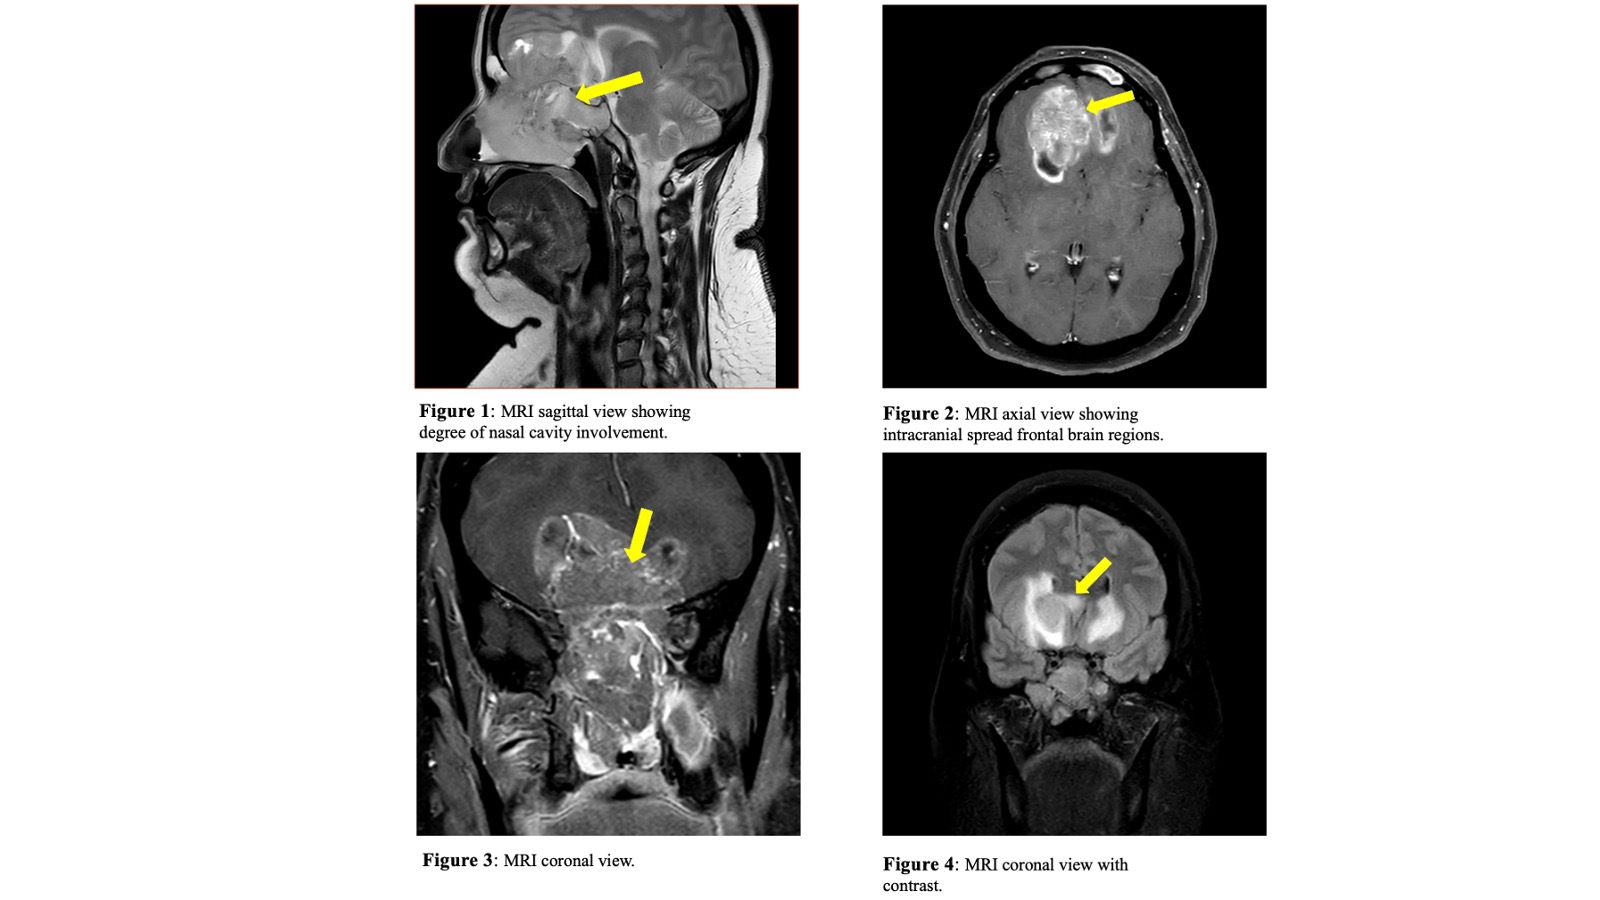

Case Presentation: A 51-year-old female with a BRCA mutation and a history of prophylactic bilateral mastectomy presented with neuropsychiatric symptoms, including confusion, memory loss, and excessive sleep. Her medical history included hysterectomy and parotid tumor resection and a family history of various cancers, including prostate, lung, and lymphoma. Initial symptoms, including headaches and nasal congestion, were treated as bacterial sinusitis. Persistent symptoms despite antibiotic treatment led to imaging, revealing an invasive mass in the nasal cavity extending into the frontal lobes. Nasal endoscopy and biopsy confirmed large cell neuroendocrine carcinoma (LCNEC) with immunohistochemical positivity for CKA1/3, CD56, synaptophysin, and CK5/6. Metastatic workup showed no distant disease. The tumor’s extensive involvement of critical structures required a collaborative surgical plan with neurosurgery and ENT skull base specialists.